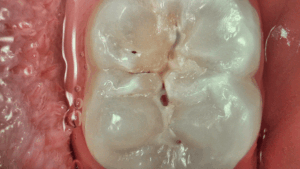

• Mode Daylight+ : Contrastes élevés mettant en exergue les fissures anatomiques et les détails de la structure/ profondeur de la dentine.